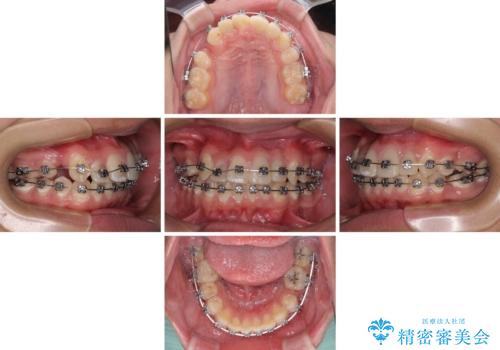

- 矯正装置

- メタルブラケット

- 治療期間

- 2年6ヶ月

むし歯が多かったため、ワイヤー矯正中に処置したむし歯が悪化することが懸念されましたが、歯磨きをしっかりと行ってくれたため、とても良好な状態を維持することができました。